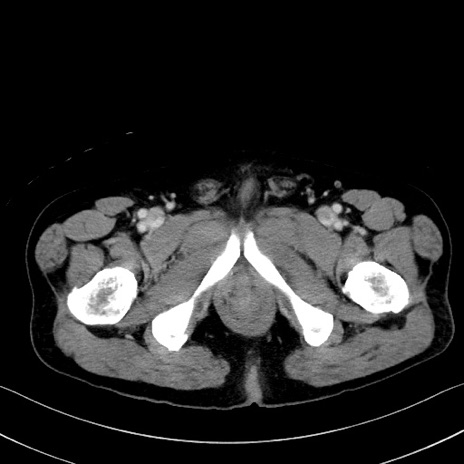

冠状断像

【症例】70歳代 男性

【主訴】腹部膨満、嘔吐

【現病歴】昨日より腹部膨満感出現。本日増悪し、仙痛出現。嘔吐あり、受診。

【既往歴】糖尿病、胆摘後

【身体所見】BP 149/80mmHg、HR 74/min、BT 35.9℃、腹部:膨満、軟、圧痛なし。腸雑音減弱あり。上腹部正中切開瘢痕あり。

【データ】WBC 13500、CRP 1.72